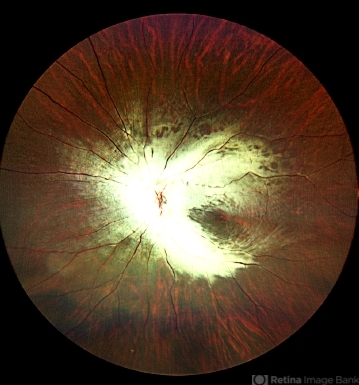

- myelinated nerve fibers

- Left eye fundus photograph of a 29-year-old male with extensive myelinated retinal nerve fibers appearing as grey white opaque lesions on the retina with feathery edges obscuring the retina.